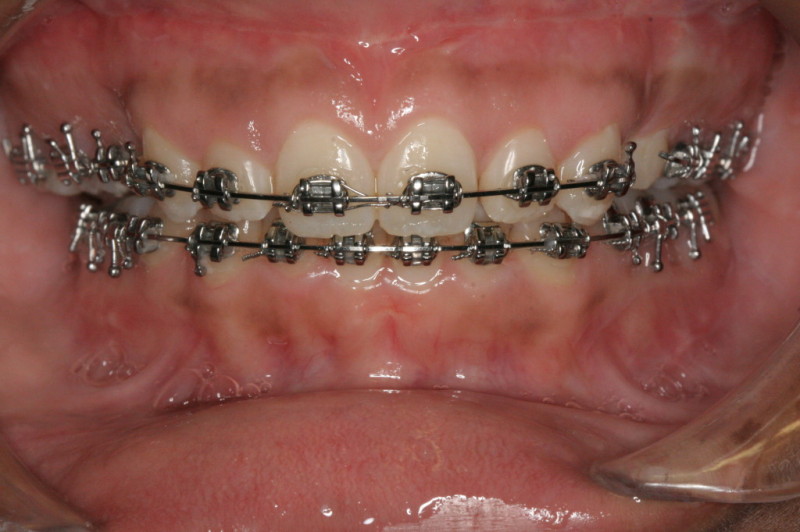

After Orthodontic Setup - Presurgical